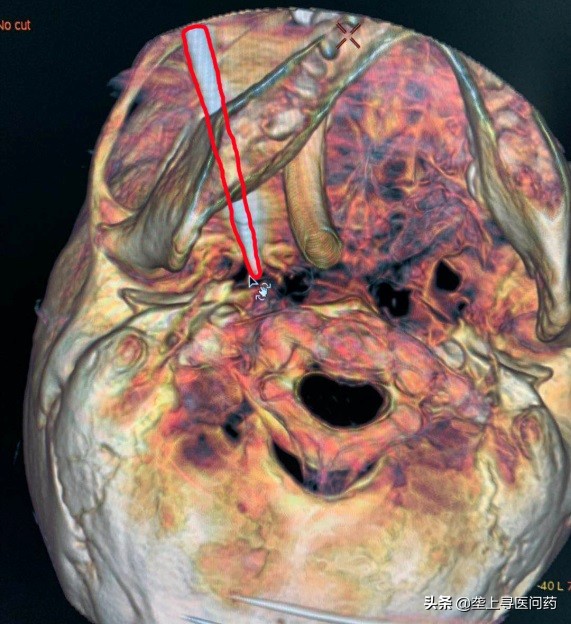

术中三维CT定位

4月3日,吴老太被推进手术室,舒凯和朱明欣博士为老太实施了微创手术。在3D造影机的实时监测下,球囊导管精确导入至三叉神经半月节,随后缓慢充盈球囊,压迫相关疼痛的神经纤维,最终完全控制疼痛症状,整个手术过程仅十余分钟。从根源上将产生疼痛解决了,吴老太面部疼痛完全消失。术后,她的脸上露出了久违的微笑。